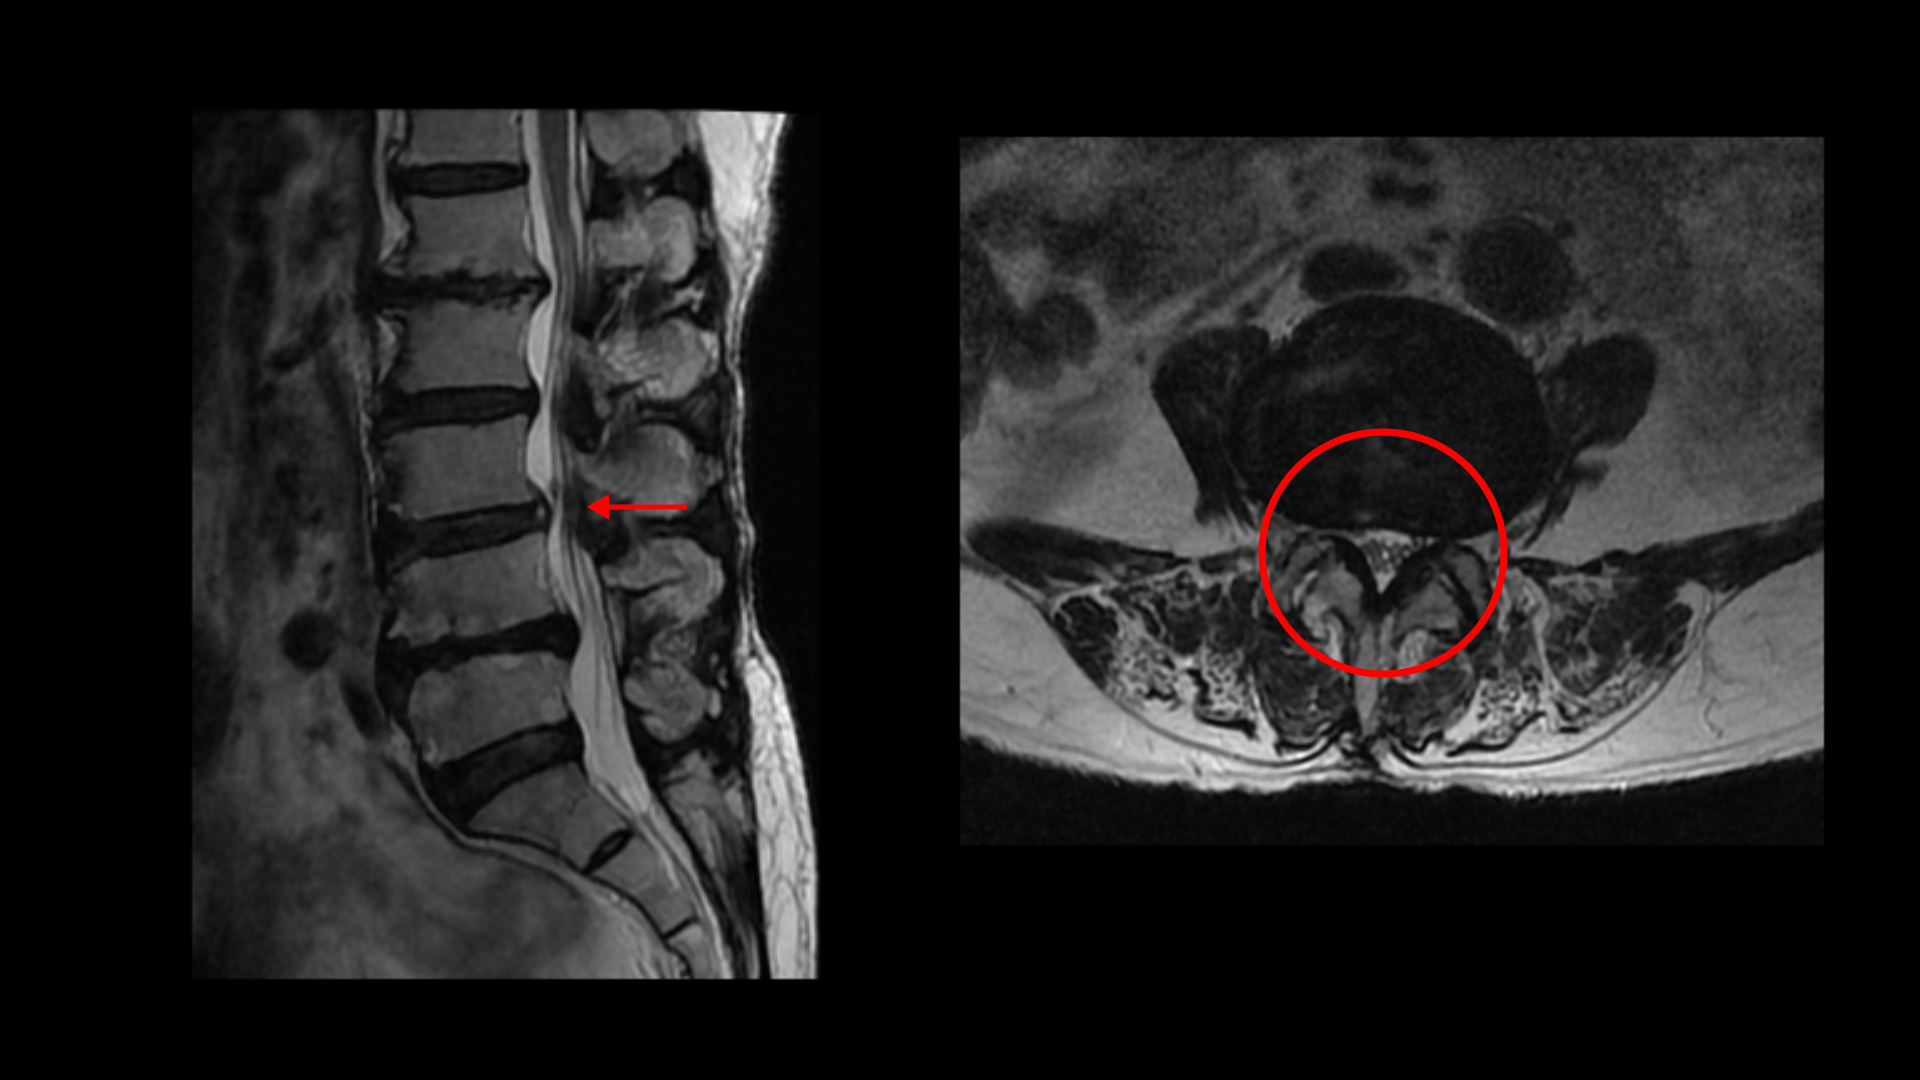

3-4번에는 중심성 협착이 있고

4-5번에는 왼쪽으로 디스크가 밀려 나와있고 심한 중심성 협착과 왼쪽 추간공협착도 있습니다.